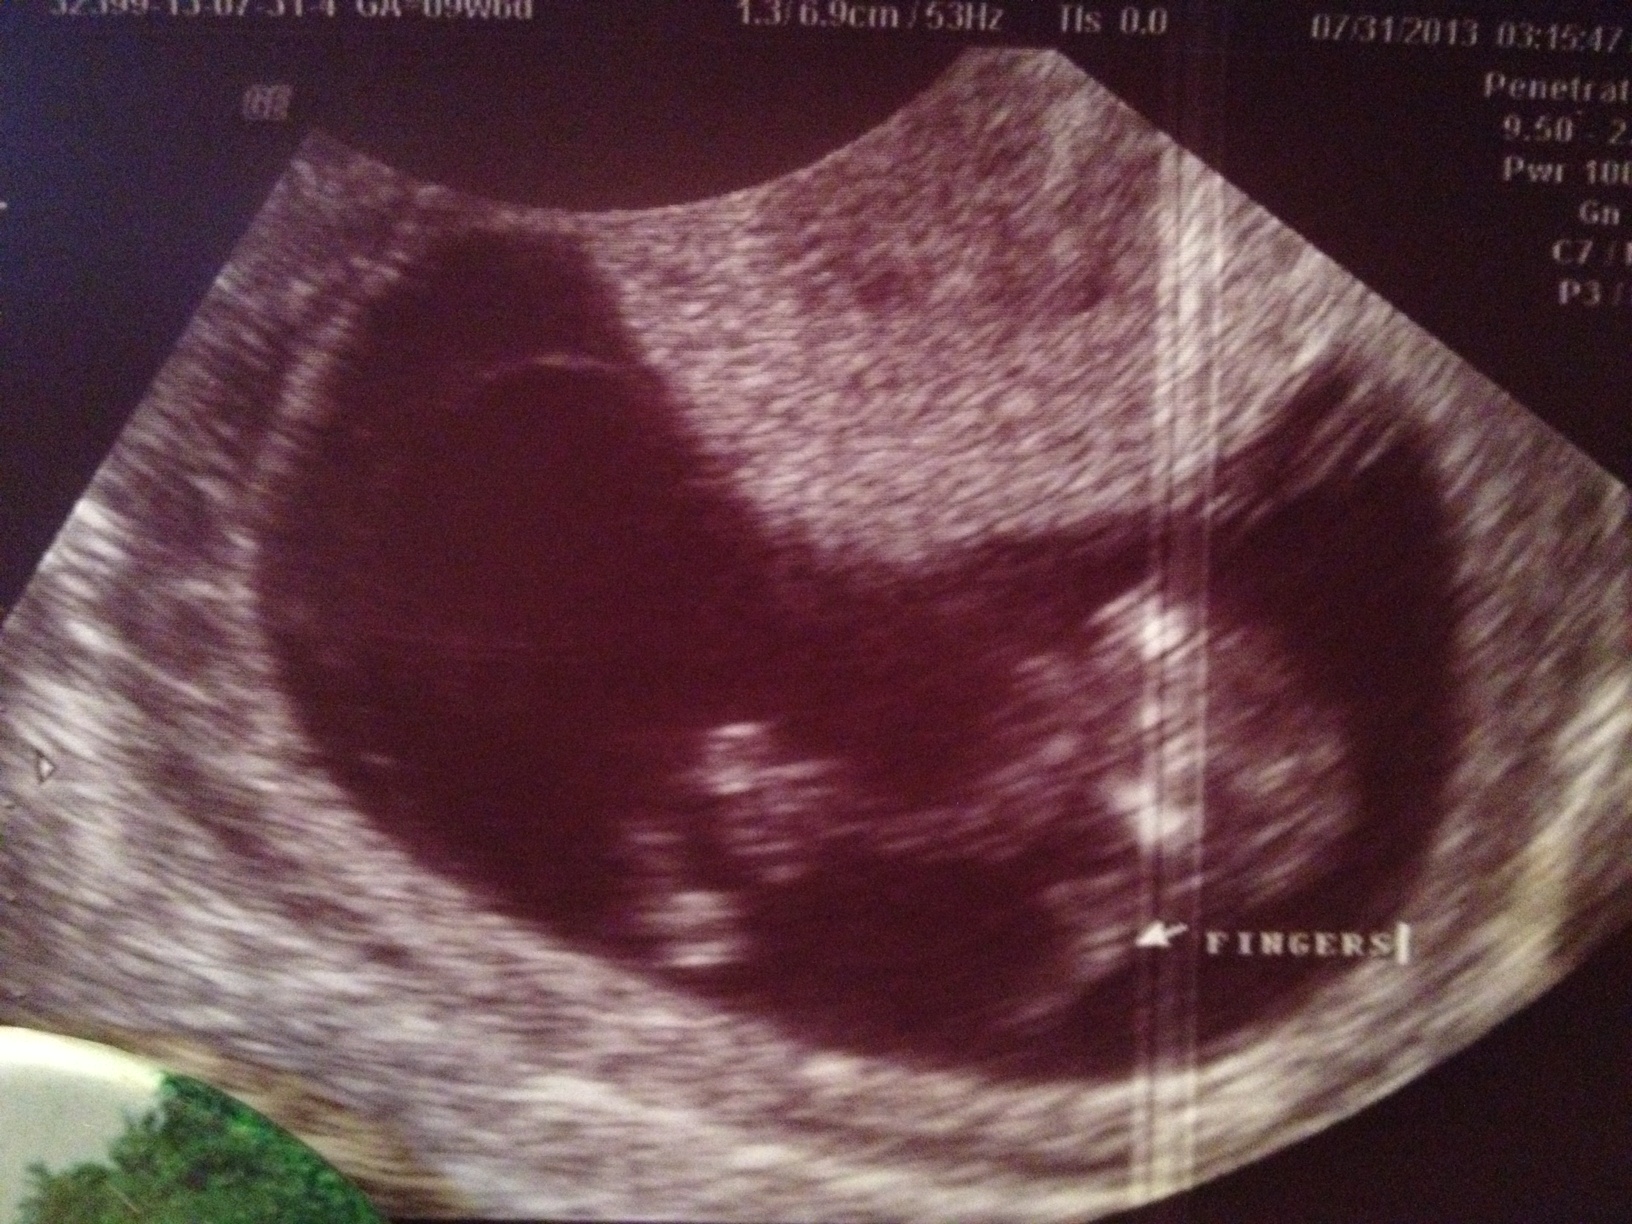

Im sorry I don't know cause its not a clear picture, I'd say that's why there's been no guesses!